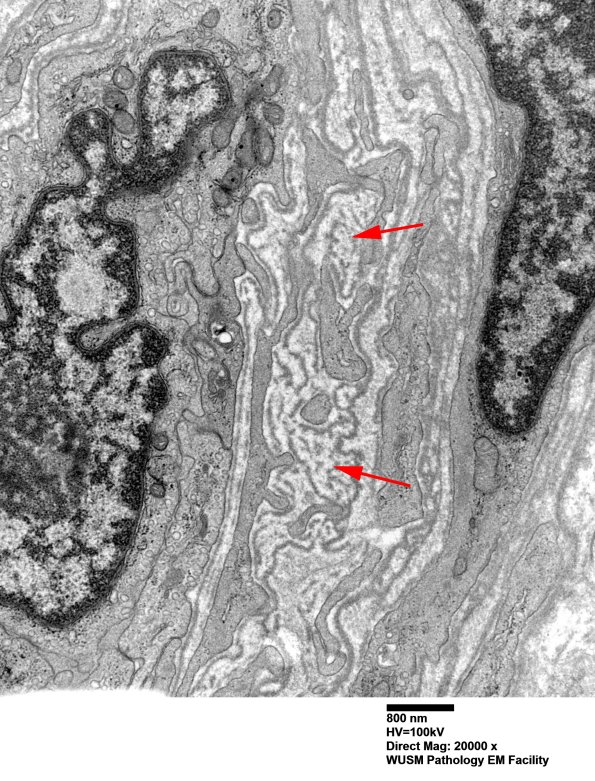

Washington University Experience | VASCULAR | Hypoxia-Ischemia, fetal-neonatal | White Matter | 16B8 (Case 16) HIEM EM027 - Copy copy

16B8 (Case 16) HIEM EM027 - Copy copy